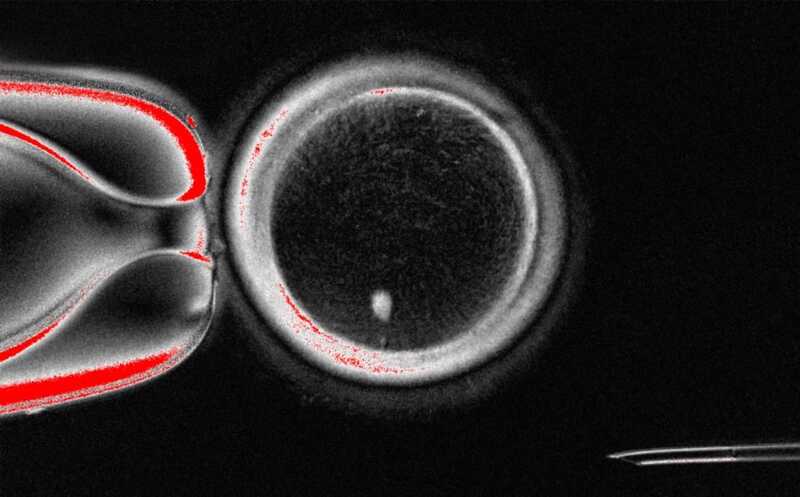

Человеческий SCNT-ооцит с веретеном деления (белая точка)

Credit:

Mitalipov laboratory | Пресс-релиз